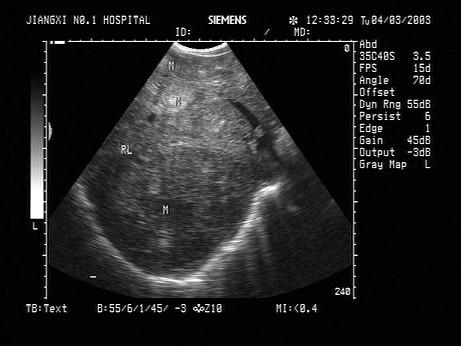

问题 患者体检发现肝脏体积增大,超声见右叶巨大的强回声光团,边界见声晕,门脉见实质性光团充填,如图所示,考虑为?(?)

选项 A.肝癌并门脉癌栓 B.肝脓肿 C.肝囊肿 D.肝结核 E.肝血管瘤

答案 A